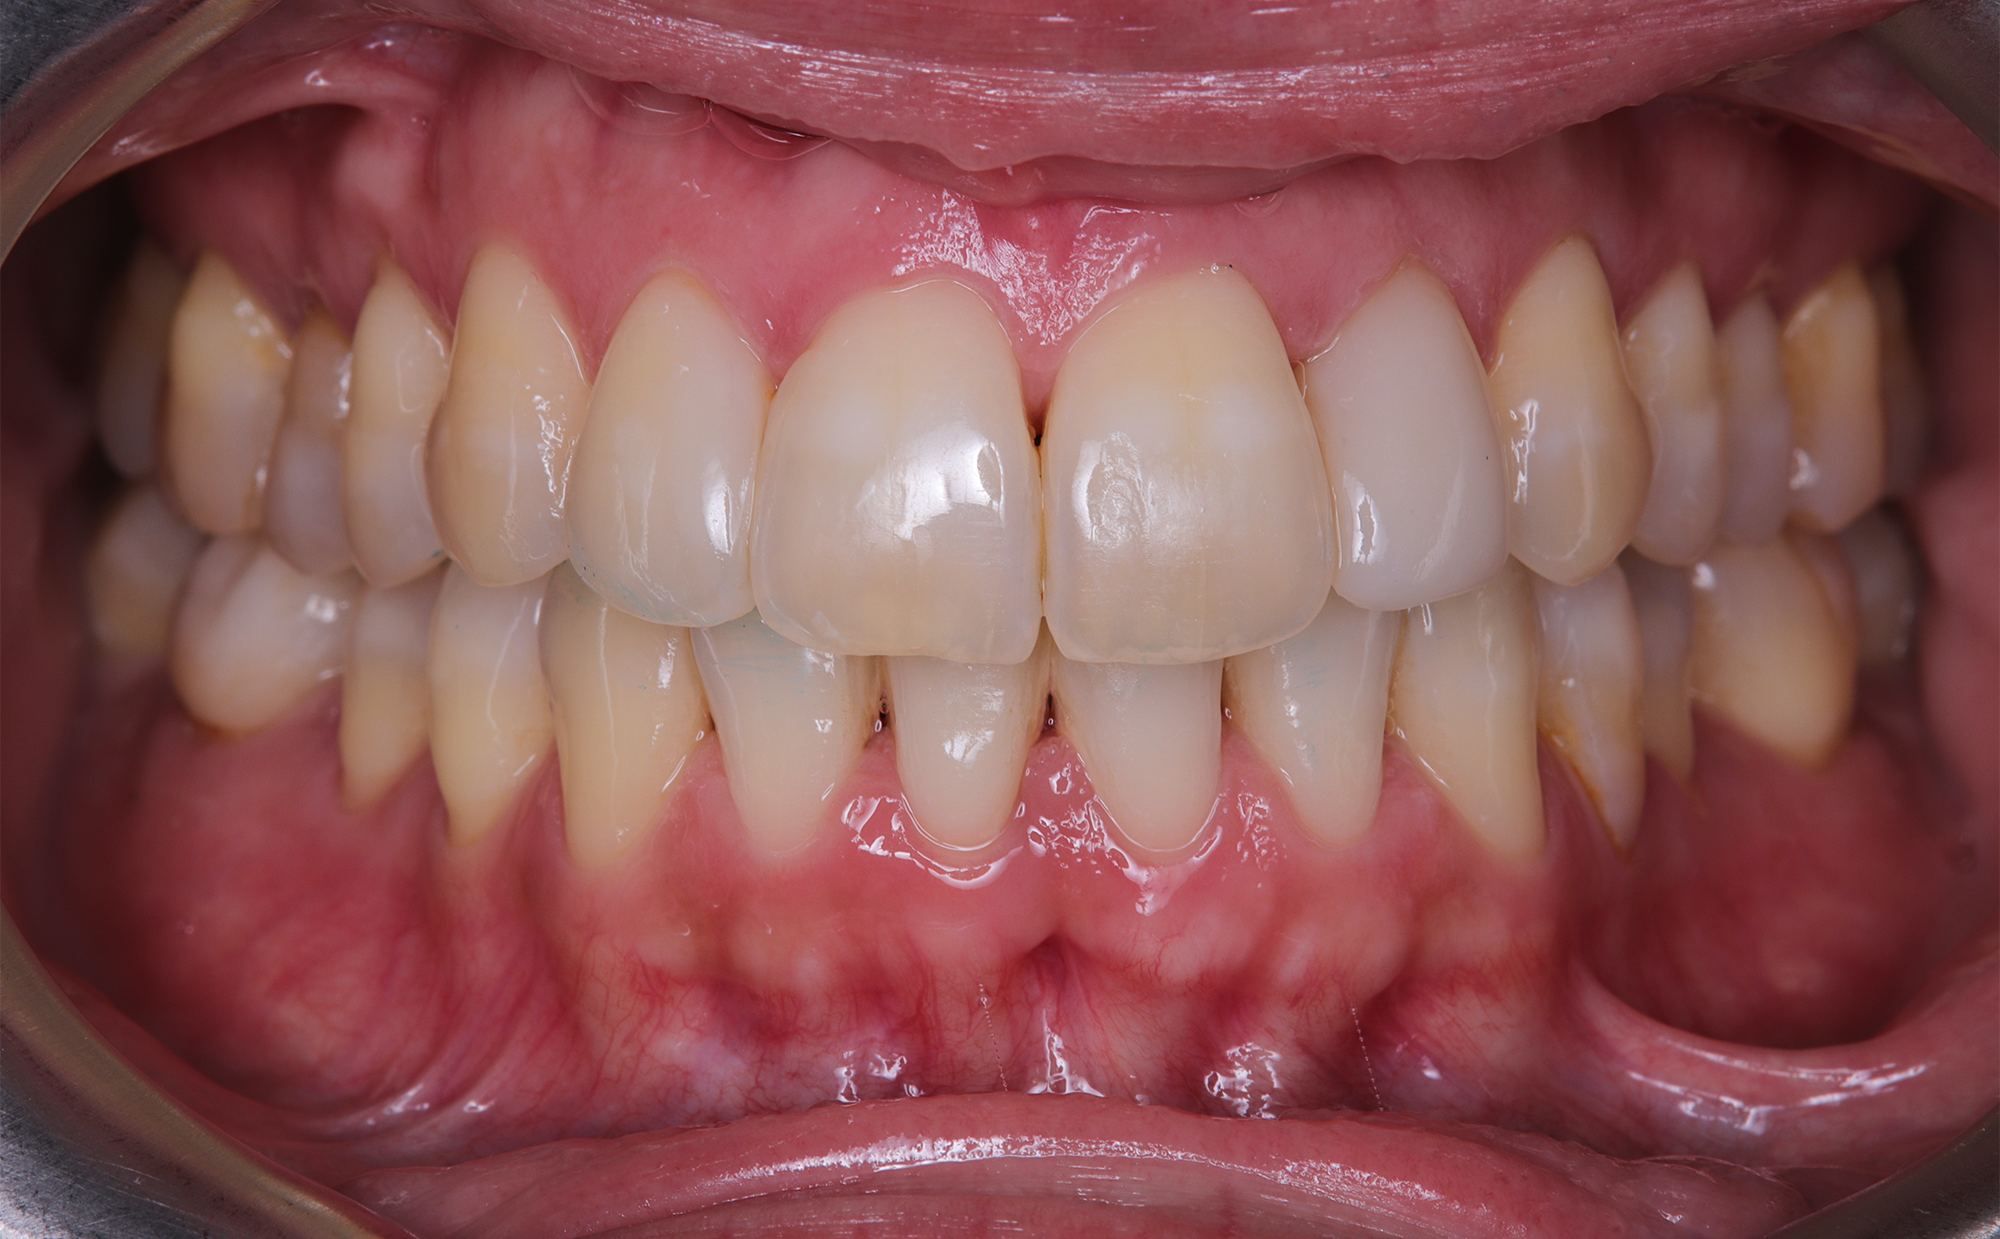

At the conclusion of the treatment, the patient achieved excellent dental alignment and a stable occlusal relationship, particularly in the anterior region. Radiographs and clinical assessments confirmed that there was no further bone loss and that previous improvements were maintained. The aesthetic enhancement from the composite restorations further contributed to the overall success of the treatment.

This case report demonstrates that in patients with a history of periodontal treatment, a carefully modulated orthodontic plan—characterized by reduced tooth movement speed and light forces—can successfully address issues of crowding and anterior crossbite while stabilizing the occlusion and supporting tissues. The favorable outcome achieved with the Spark Advanced system, along with strategic IPR and restorative composite application, supports the adoption of conservative orthodontic protocols focused on occlusal and tissue stability.